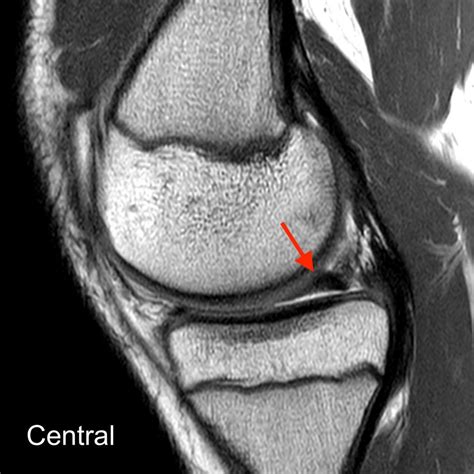

A Bucket Handle Meniscus Tear is a specific type of meniscus tear where a longitudinal tear occurs, causing a portion of the meniscus to displace and flip into the joint space. This displacement can resemble the handle of a bucket, hence the name. This type of tear is often more severe than other types of meniscus tears and can lead to significant knee instability and pain.

• Imaging Tests: Magnetic Resonance Imaging (MRI) is the gold standard for diagnosing meniscus tears. It provides detailed images of the knee joint, allowing for accurate identification of the tear.